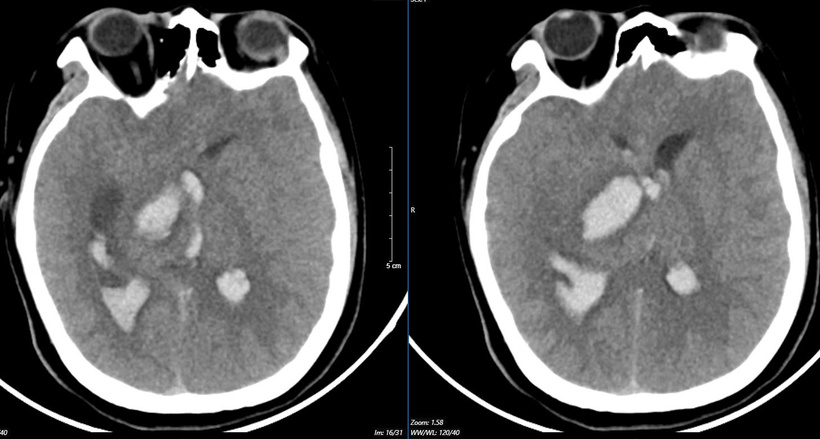

Tình trạng của bệnh nhi khi vào Trung tâm Đột quỵ, Bệnh viện Bạch Mai, ý thức hôn mê sâu, Glasgow 5 điểm, thở máy, giãn đồng tử bên phải. Kết quả chụp lại phim MSCT mạch não chảy máu não đồi thị - não thất do vỡ khối AVM (dị dạng thông động- tĩnh mạch não) biến chứng giãn não thất cấp, rối loạn thân nhiệt, sốt cao liên tục 39 - 40 độ C. Khối dị dạng mạch não tuy không quá lớn nhưng ở vị trí cực kỳ nguy hiểm.

Hình ảnh chụp phim MSCT mạch não chảy máu não đồi thị - não thất do vỡ khối AVM (dị dạng thông động- tĩnh mạch não) bệnh nhân 15 tuổi. Ảnh: BVCC